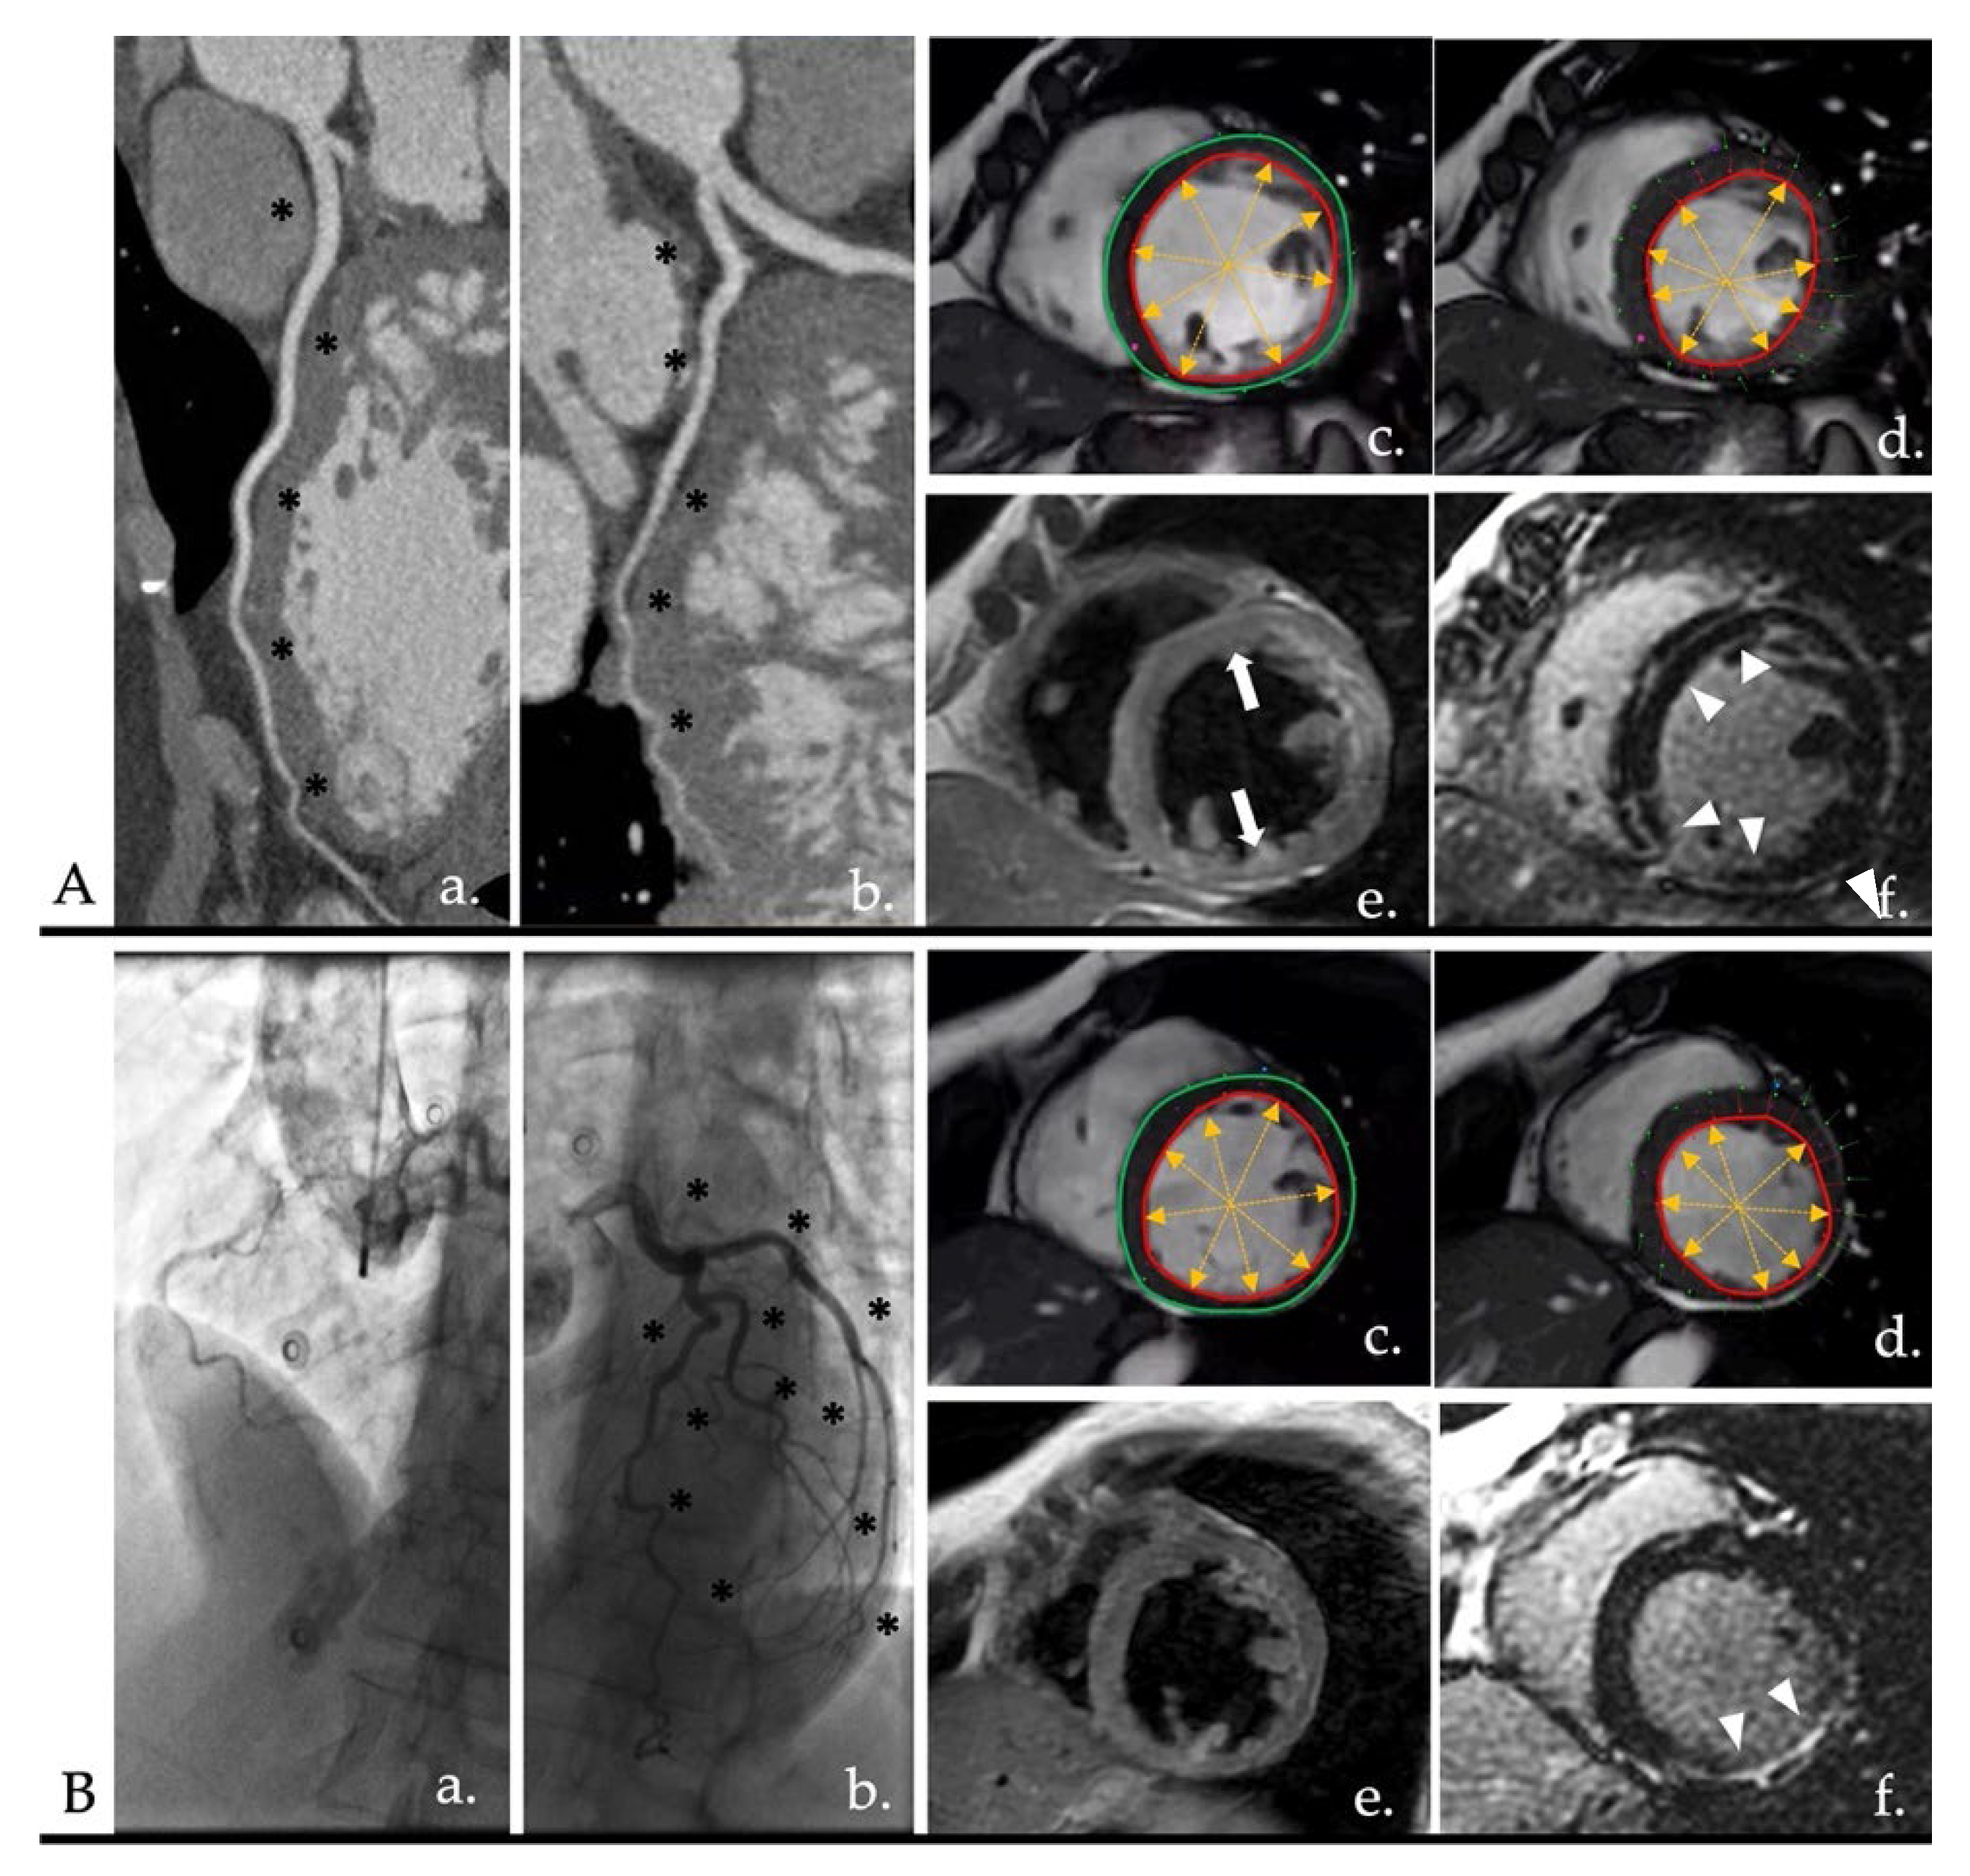

3.1. Ischemic Heart Disease (IHD)

3.1.1. Acute Coronary Syndrome

3.1.2. Chronic Coronary Syndrome (CCS)

3.1.3. Imaging Tips